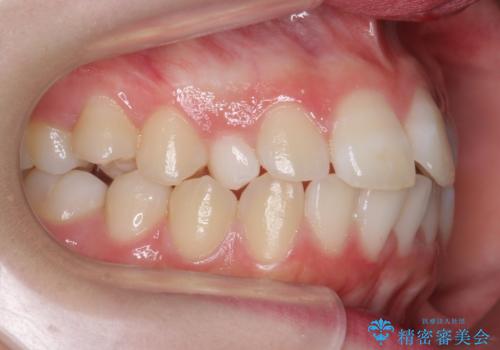

前歯のがたつき 乳歯を抜かずに矯正

- 前歯のがたつきを主訴に来院。

右上に乳歯が残っていましたが、後継永久歯がないため、抜かずに矯正しました。

乳歯の部分が反対咬合でしたが、歯列矯正で被蓋が改善するように移動させました。

右上の乳歯は移動させましたが、幸い矯正後にぐらつくこともなく、そのまま抜けるまで使うことにしました。